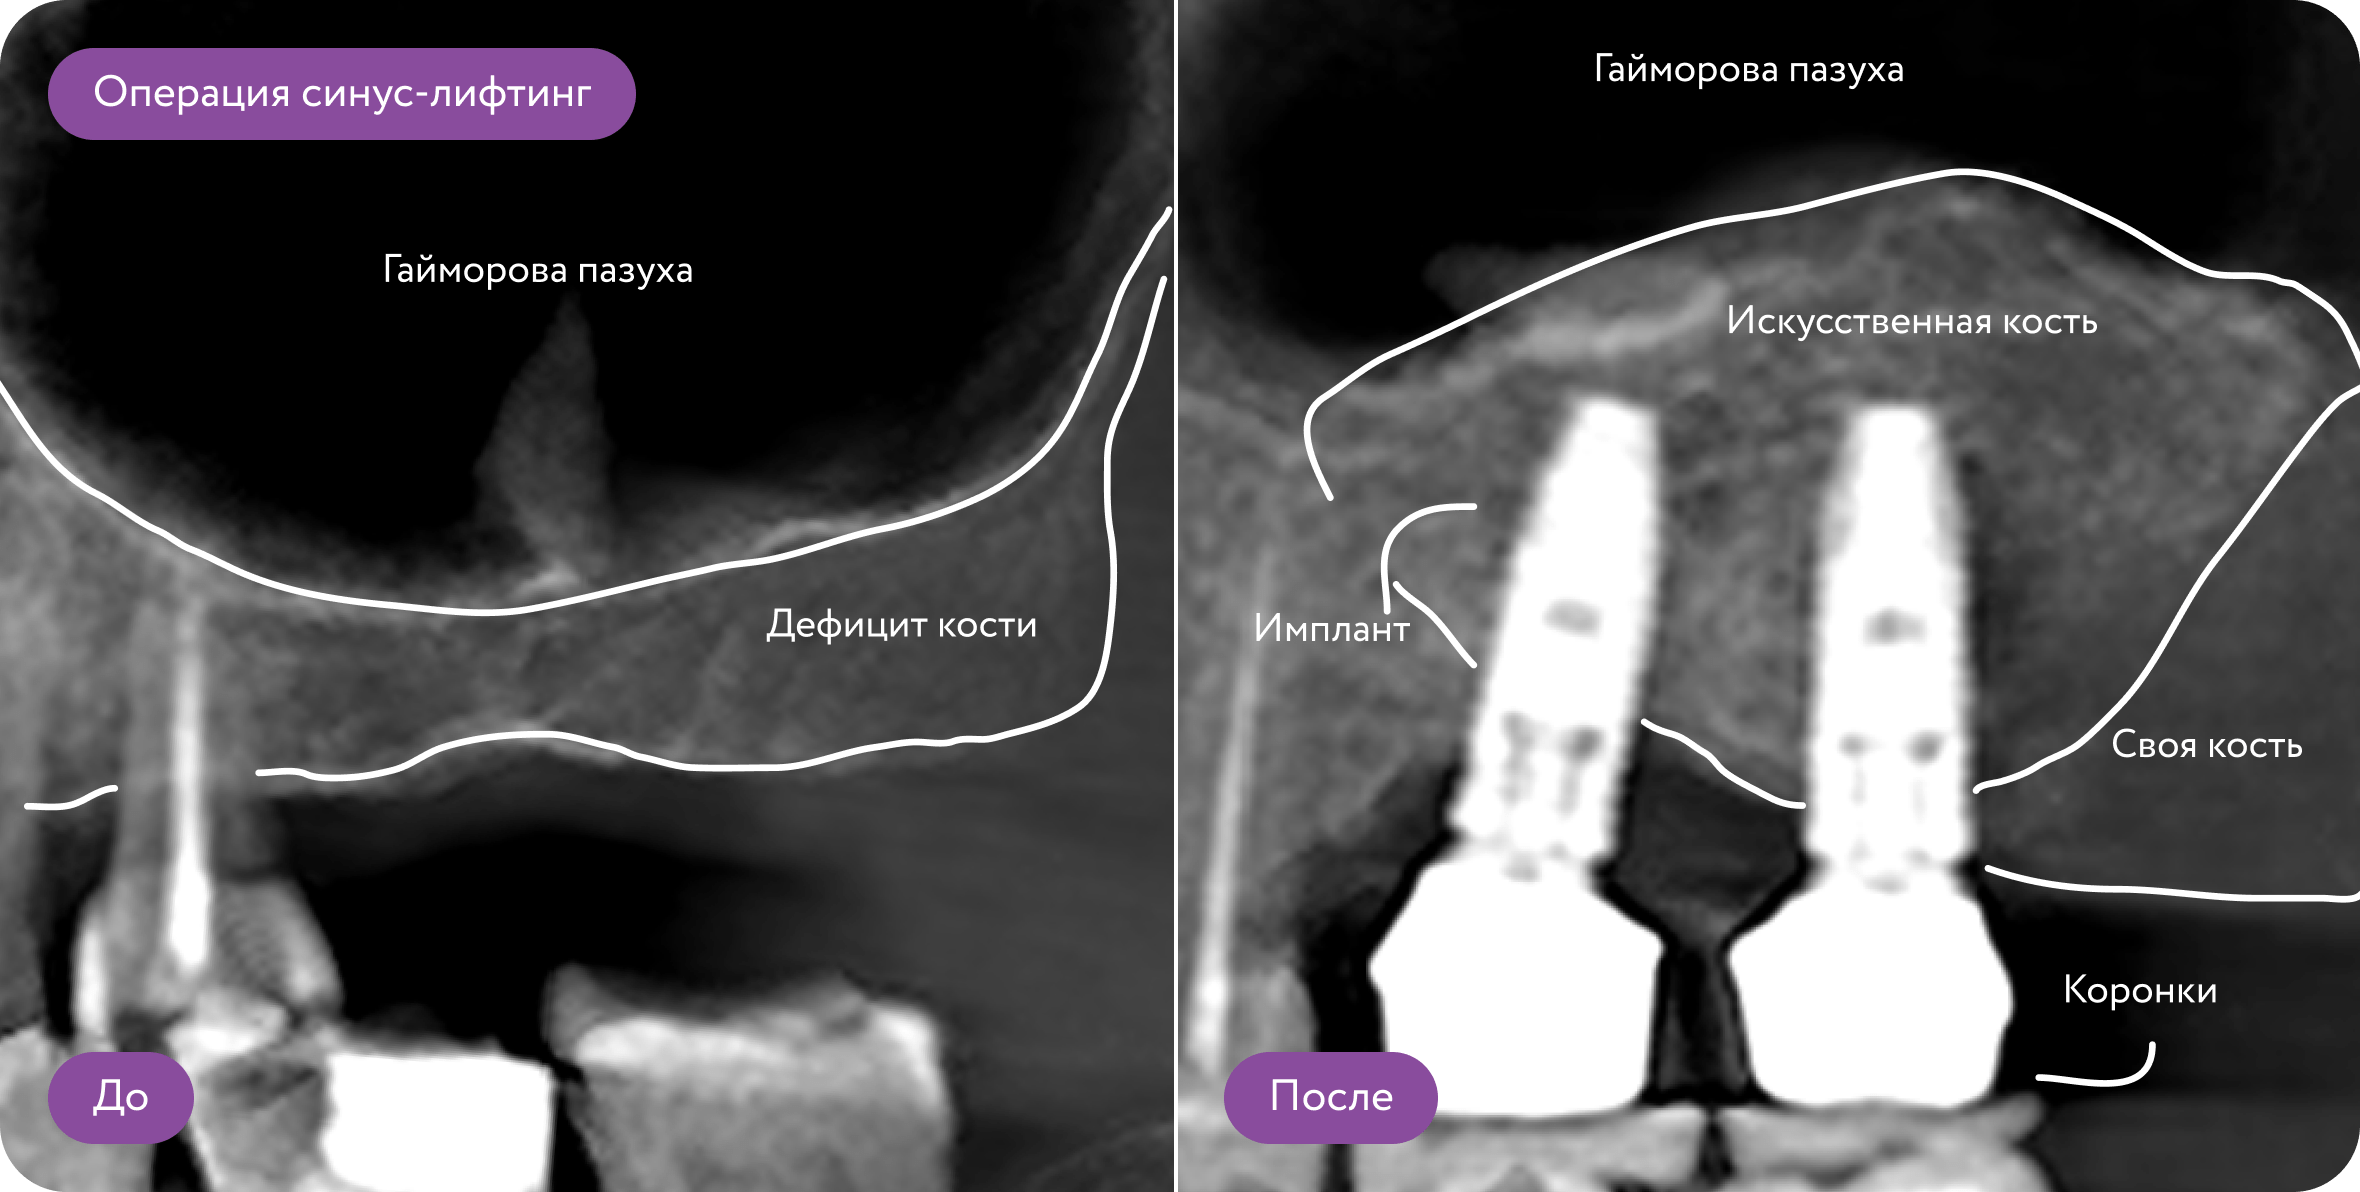

Синус-лифтинг - операция по наращиванию костной ткани на верхней челюсти

В 80% случаев после удаления зубов на верхней челюсти, кость атрофируется под действием давления со стороны пазух, и невозможно установить импланты

Для чего делают костную пластику?

Часто бывает, что после удаления зуба кость атрофируется, и нет условий для установки импланта. Требуется костная пластика - наращивание костной ткани с использованием искусственного костного материала